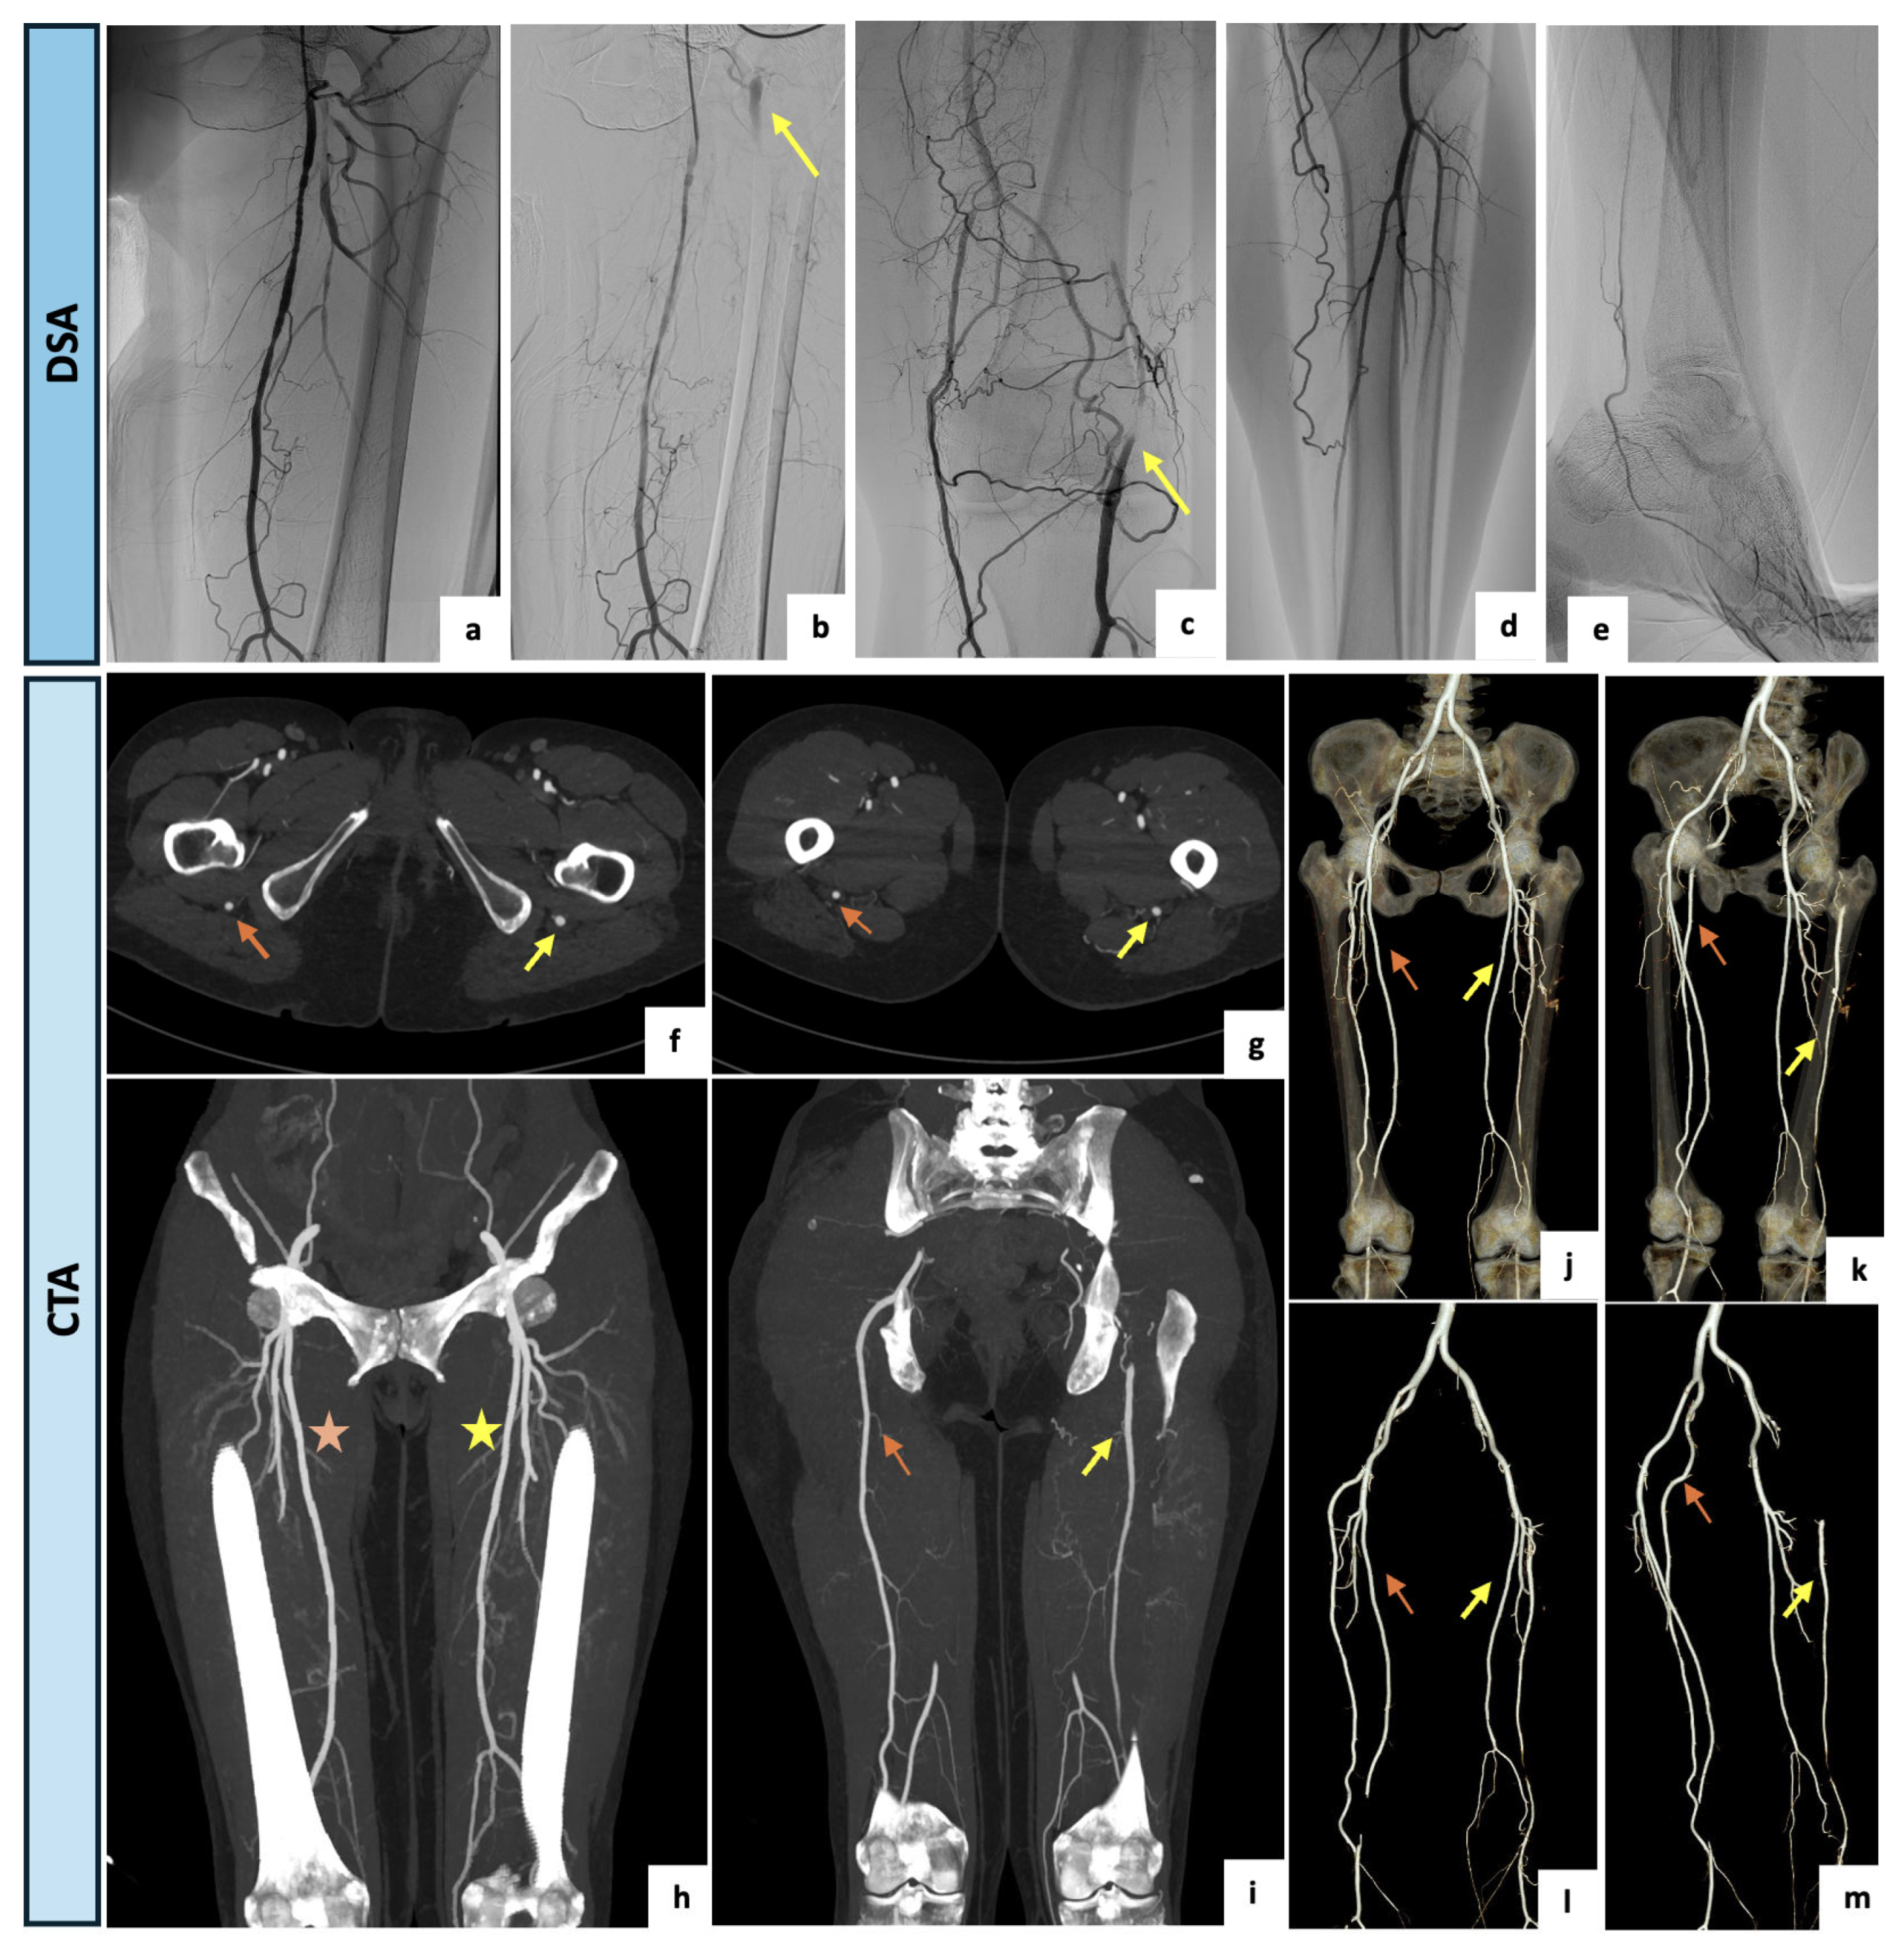

A 61-year-old woman was referred to the outpatient clinic of the Vascular Surgery Department for a type IIb bilateral claudication of her lower extremities with a recent worsening on the left side. The patient had a clinical history of active cigarette smoking, arterial hypertension, type 2 diabetes and moderate-to-severe renal impairment (eGFR of 29.9 mL/min/1.73 m2). Right peripheral pulses were present whereas on the left side the femoral pulse was diminished, and distal pulses were not palpable. Perfusion, sensation and motor function were bilaterally maintained. The arterial DUS of the lower limbs showed a complete occlusion of the left SFA at the Hunter’s canal with a restoration of blood flow at the level of the articular tract of the popliteal artery, where a monophasic and low peak systolic velocity flow was detected. On the right lower limb, physiological popliteal and tibial flow were assessed. After a multidisciplinary discussion of the clinical case, a primary angiographic approach with attempted left SFA revascularization was indicated with the aim of reducing the contrast medium burden. After an adequate periprocedural hydration protocol and under local anesthesia, a left antegrade common femoral access was obtained. The preliminary selective digital subtraction angiography showed a hypoplasic and interrupted left SFA, lacking the usual continuation. The popliteal artery was instead supplied by collateral pathways originating from distal small branches of the SFA and the deep femoral axis. Surprisingly, an arterial vessel suggestive of incomplete PSA was retrograde perfused via deep femoral collateral pathways and visualized both proximally and distally as brief tracts. Due to the incidental finding of the PSA, the case was rediscussed, and CTA was accordingly indicated. Upon CTA examination (Figure 5), a bilateral PSA was found. On the left side, a type 2A PSA with a proximal focal occlusion and re-habitation via gluteal collateral pathways, as well as a distal femoral significant stenosis, were detected. The right lower limb presented a type 1 complete PSA. The patient was thus submitted to a medical management program consisting of smoking cessation, exercise training, glucose-lowering therapy, anti-platelet agents and cilostazol, with an initial slight improvement of symptoms. Since the PSA assumed a dominant role as the main blood supplier to the left lower limb, the patient qualifies as a candidate for endovascular recanalization with PSA angioplasty if symptoms worsen or persist.

Figure 5.

(a–e) Intraprocedural selective angiographic images obtained after a left antegrade common femoral access. (a–e) The angiograms demonstrate a diffusely hypoplasic and interrupted left SFA, lacking the usual continuation, and a popliteal artery supplied by collateral pathways originating from the distal small branches of the SFA and the deep femoral axis. (b,c) Surprisingly, an arterial vessel suggestive of incomplete PSA was retrograde perfused via deep femoral collateral pathways and visualized both proximally and distally as brief tracts (yellow arrows). (f–i) Axial and coronal maximal intensity projection views of the CTA confirming a bilateral PSA. On the left side, a type 2A PSA (yellow arrows) and a distal significant stenosis of the SFA (yellow asterisk) were detected. The right lower limb presented a type 1 complete PSA (orange arrow) along with a regular SFA (orange asterisk). (j–m) Three-dimensional reconstructions with and without bone structures. On the left side, a type 2a PSA with a proximal focal occlusion and re-habitation via gluteal collateral pathways, and a distal femoral significant stenosis was detected (yellow arrows). The right lower limb presented a type 1 complete PSA (orange arrows).